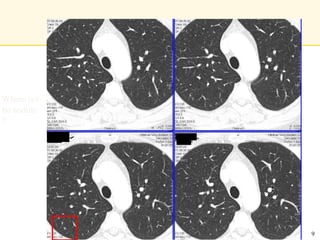

Where is t

he nodule

?